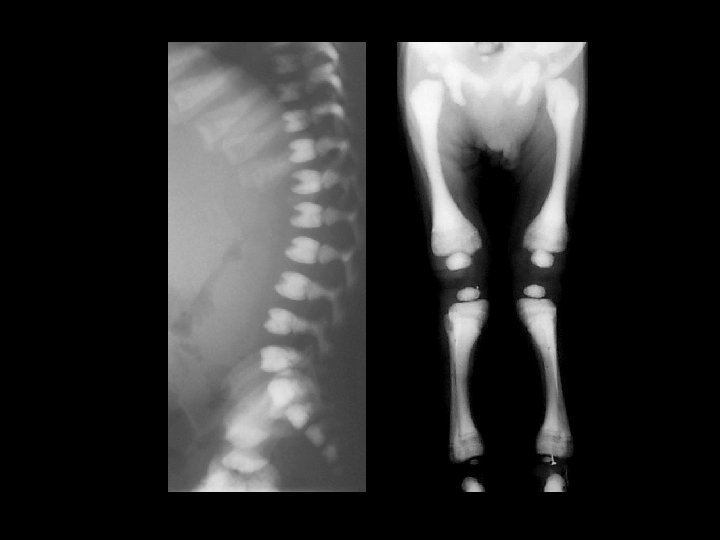

Rickets • Findings: – Cupped and frayed metaphyses – Wide physes (increased osteoid) – Long bone bowing – Decreased bone density • ddx: – NONE! – This is an Aunt Minnie!